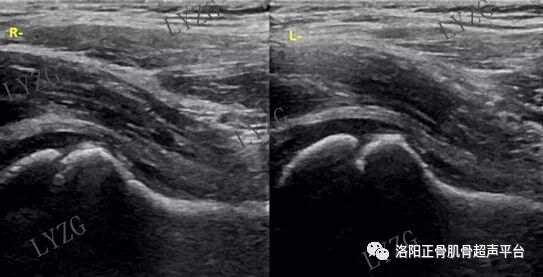

小儿髋关节滑膜炎超声表现

左侧髋关节前隐窝内积液并滑膜增生(呈不规则条带状)

右侧髋关节前隐窝内积液并滑膜增生(呈不规则团块状)